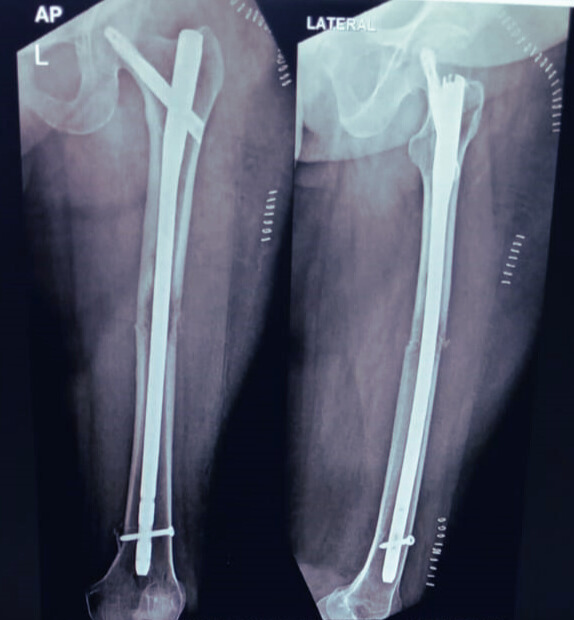

Intraoperative fluoroscopy confirmed excellent fracture reduction and stable PFNA placement. Postoperative imaging further validated the implant’s optimal position, ensuring strong fixation and supporting a confident, accelerated recovery.

Postoperative image & Recovery:

X-ray demonstrating accurate PFNA placement across the transverse femoral fracture